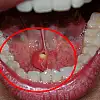

Taşların ağızdan dışarı atılmasındaki yöntemler hakkında da bilgilendirmede bulunan Doç. Dr. Nesrettin Fatih Turgut, “Bu hastalıkta tipik belirti, taşın var olduğu tarafta yer alan bezde yemek yeme sonrası gelişen şişlik ve ağrıdır. Tükürük salgısının dışarı atılamayıp birikimi, enfeksiyona yatkınlık oluşturur. Bakteriyel tükürük bezi iltihabı dediğimiz hastalık gelişebilir ki bu durumda şikayetler şiddetli hale gelebilir. Etkilenen tükürük bezinin aşırı şişmesi, aşırı hassasiyeti, ağrı ve ateş gelişebilir. Tedavi edilmediği takdirde, hastane yatışı gerektiren ve şiddeti daha fazla olan bir tabloya, derin boyun enfeksiyonuna, ilerleme görebiliriz. Şikâyetleri daha hafif olan ve taş boyutları küçük ve tükürük bezi kanalının ucuna yakın yerde yerleşim gösteren hastalarda geleneksel tedaviler önerilir. Ağrı kesiciler fayda sağlar. Bol sıvı tüketimi, ısı uygulaması rahatlama sağlayabilir. Bol sıvı tüketimini tüm hastalarımızda önermekteyiz. Aynı zamanda limon gibi ekşi ürünlerin emilmesi tükürük sıvısını artırır ve çok küçük taşların dışarı atılmasını sağlayabilir. Taş boyutunun büyük olması, taşında daha çok beze yakın yerde yerleşmiş olması durumlarında ise cerrahi uygulamaları gündeme gelmektedir. Taş yerleşimi, büyüklüğü etkilenen tükürük bezinin durumu cerrahinin şeklini belirler. Eğer taş tükürük bezi kanalında yer alıyorsa, sialendoskopi olarak adlandırılan kamera sistemi ile yer tespiti ve çıkarma işlemi herhangi bir kesi olmaksızın tercih edilir. Ancak taşın tükürük bezi içerisinde yer alması, boyutunun çok büyük olması durumlarında ise dışardan veya ağız içinden yaklaşım ile cerrahi seçenekleri gündeme gelmektedir” diye konuştu.

Tedavi yöntemlerinden de bahseden Turgut, “Sialendoskopi, genellikle tükürük kanallarında taş olan hastaların tedavisinde kullanılmaktadır. Ayrıca sjögren hastalığı, radyoaktif iyot tedavisi almış hastalar ve tekrarlayan tükürük bezi iltihaplarına sahip çocuk hastalarda da bu yöntem uygulanabilir. Büyük taşlar havalı kırma tekniği kullanılarak küçültülerek çıkarılır, bu nedenle işlem süresi uzun olabilir. Sialendoskopi sırasında herhangi bir kesi veya dikiş uygulanmaz, bu nedenle işlem sonrasında ağrı veya şikâyet gözlemlenmez. Geçici olarak aynı taraftaki tükürük bezinde şişlik olabilir, ancak genellikle bu şişlik 1-2 saat içinde azalır. Hastalar, genellikle aynı gün içinde taburcu edilirler. Taş boyutunun büyük olması, taşın bez içinde yerleşim göstermesi, sık enfeksiyona bağlı taşın kanala yapışık olması gibi nedenlerden dolayı sialendoskopi ile taşın çıkarılması mümkün olmayabilir. Bu durumlarda açık cerrahi seçeneği gündeme gelir. Eğer taş, kanal içinde yerleşim gösteriyorsa ağız içerisinden kanal üzerinde yapılacak ufak bir kesi ile taşa ulaşılır ve taş çıkarılır. Birkaç dikiş atılarak işlem tamamlanır. Hastalarımız ancak taş tükürük bezi içinde olursa veya tükürük bezi sürekli (kronik) enfeksiyona bağlı olarak işlevini yitirmişse (atrofiye uğramış) tükürük bezi genel anestezi altında çene altından kesi yapılarak tamamen çıkarılır. Ameliyat sonrası 2-3 gün hastane yatışı gerekebilir” şeklinde konuştu.